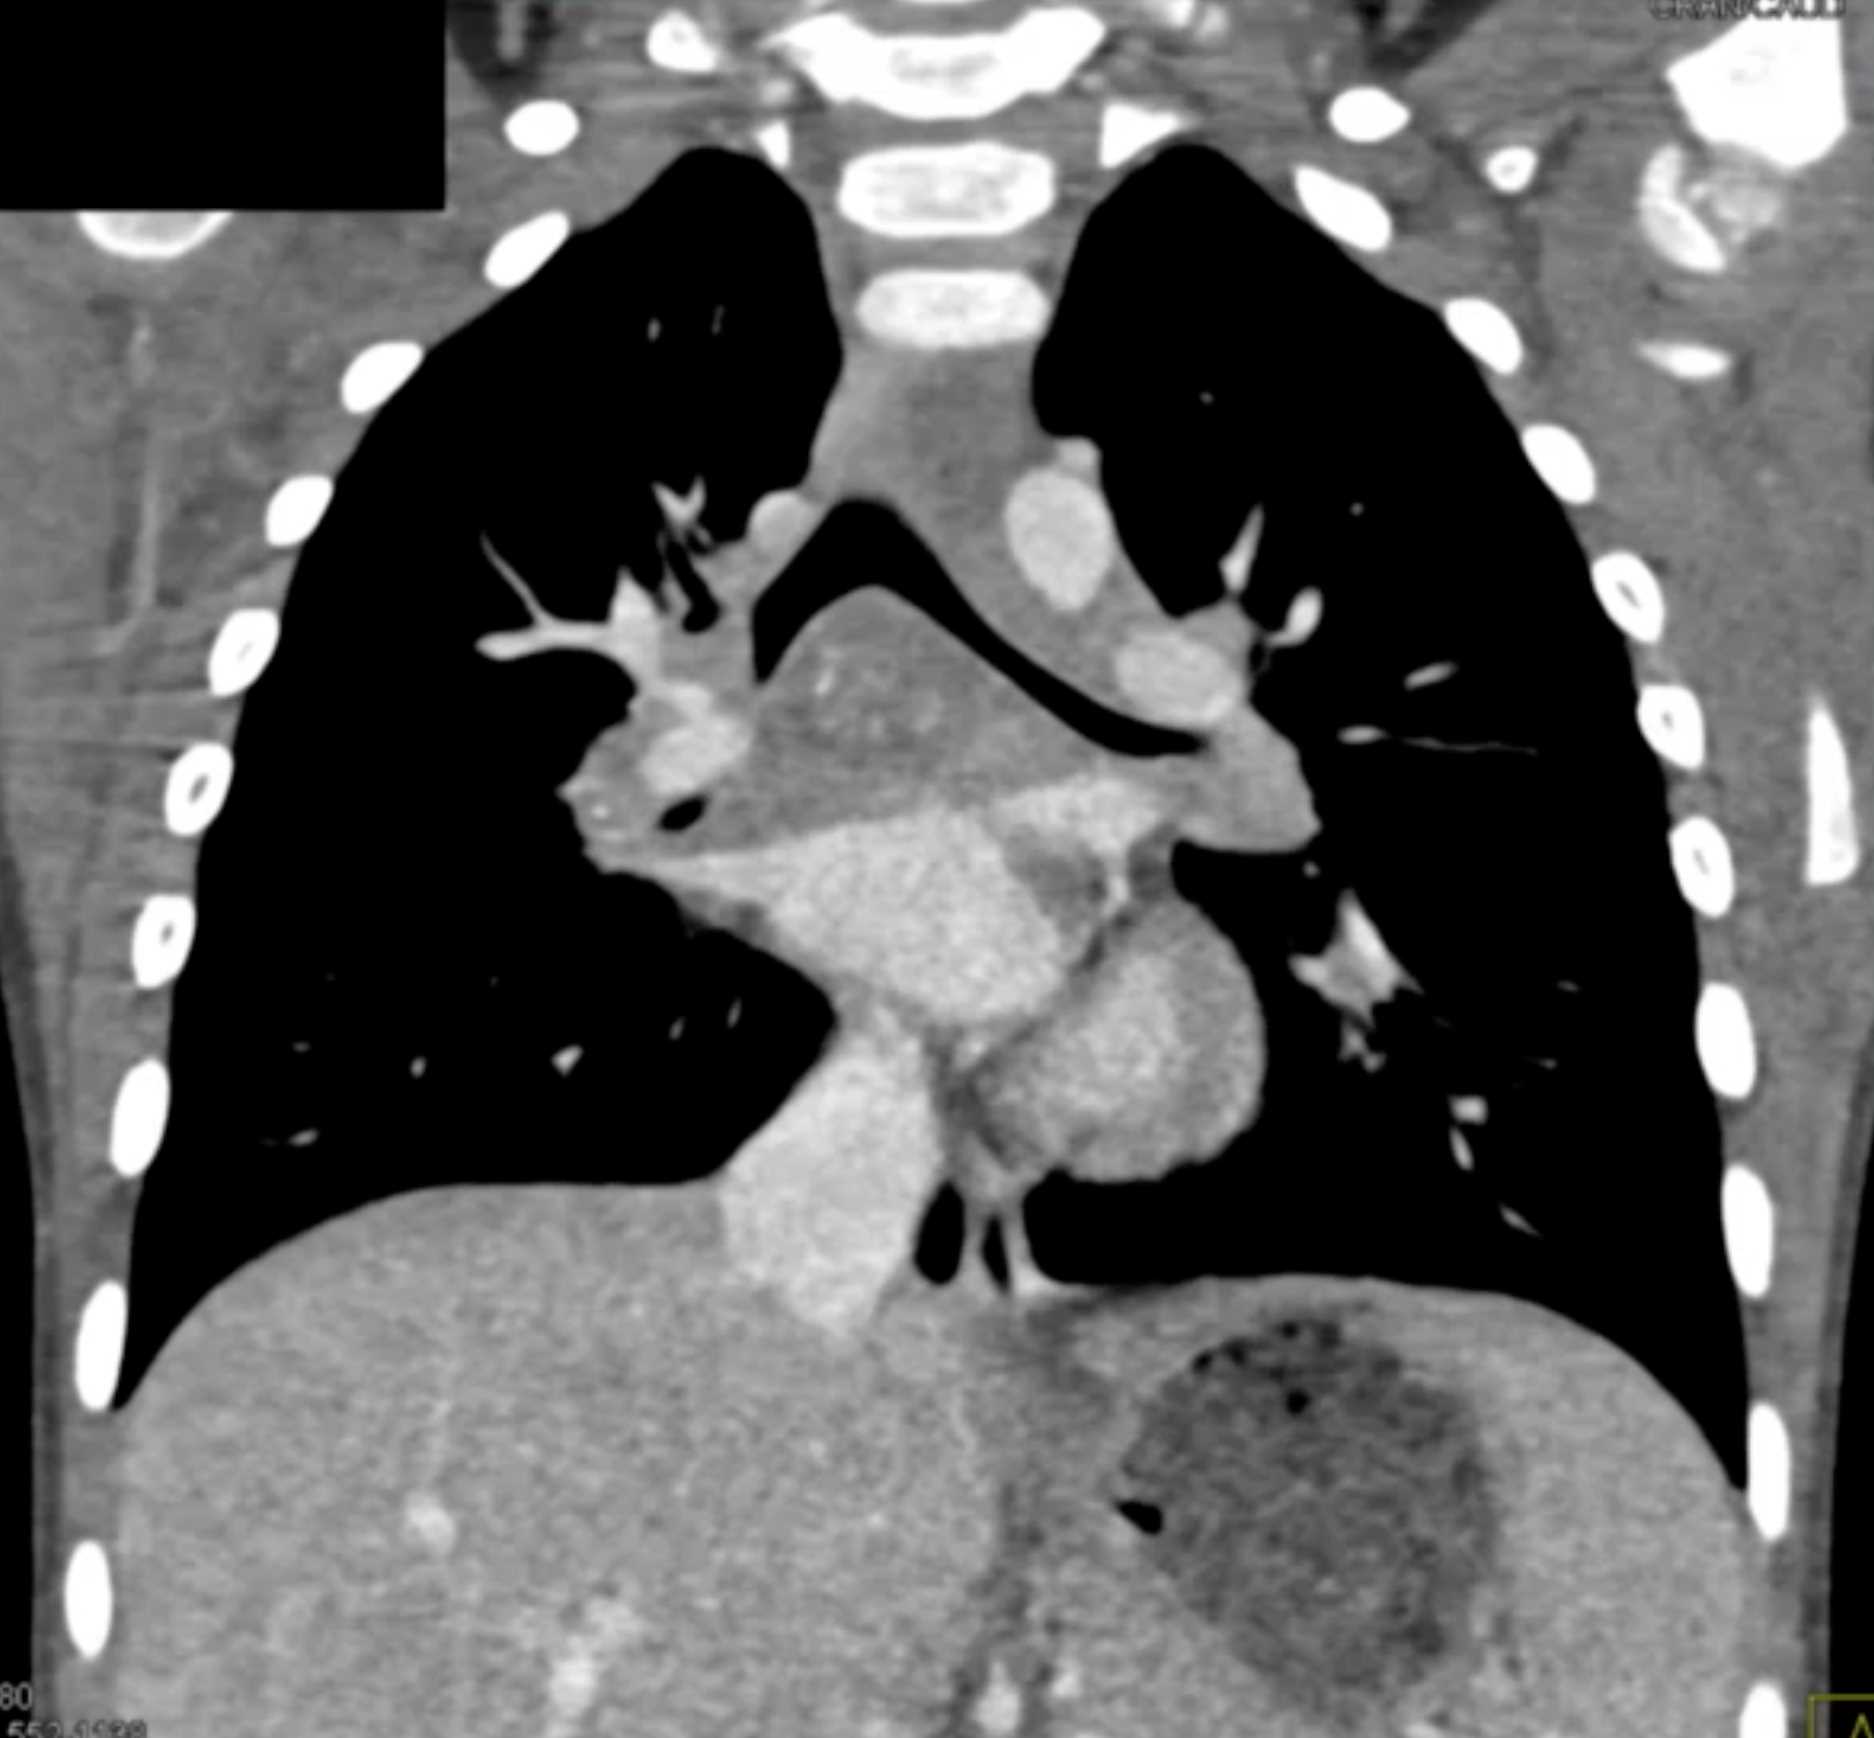

Histoplasmosis and Normal Thymus